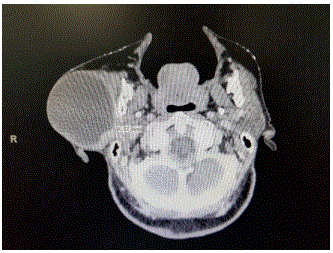

Imagem abaixo pertence a uma mulher de 82 anos, que relata ter a lesão há mais de 10 anos. Refere crescimento lento e sempre teve medo de operar, por isso nunca procurou assistência médica. Nega dor, atualmente refere apenas incomodo pelo volume local. Com base nestas informações qual a resposta correta?

enunciado 1543040-1